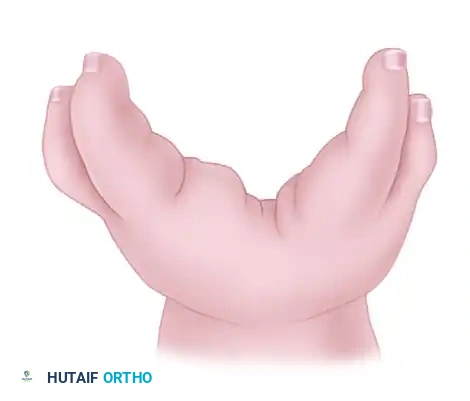

Central longitudinal deficiencies of the hand, historically termed "cleft hand" or "ectrodactyly," represent a complex spectrum of congenital anomalies characterized by the suppression or absence of the central rays (typically the long finger and third metacarpal). These deformities present significant functional and aesthetic challenges, requiring a nuanced, highly individualized surgical approach.

Present at birth, this pattern features a central V-shaped defect in the palm. The long finger is usually entirely absent. The remaining digits bordering the cleft (index and ring fingers) frequently exhibit varying degrees of syndactyly and a deficient, narrowed first web space. The deformity is often bilateral and inherited in an autosomal dominant pattern with variable penetrance. Foot deformities (cleft foot) are frequently associated.

Children with central hand deficiencies often develop remarkable compensatory dexterity. However, the psychological impact of the "clawlike" appearance becomes pronounced as the child enters grade school.